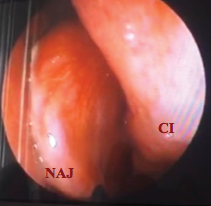

En el consultorio se realizó nasofibrolaringoscopia observándose masa pálida dependiente del cornete medio izquierdo en alto contacto con el cornete inferior izquierdo (Figura 4).

Figura 4. NAJ Nasoangiofibroma Juvenil. CI[Cornete inferior]. Fuente: Hospital Militar Central de Bogotá.